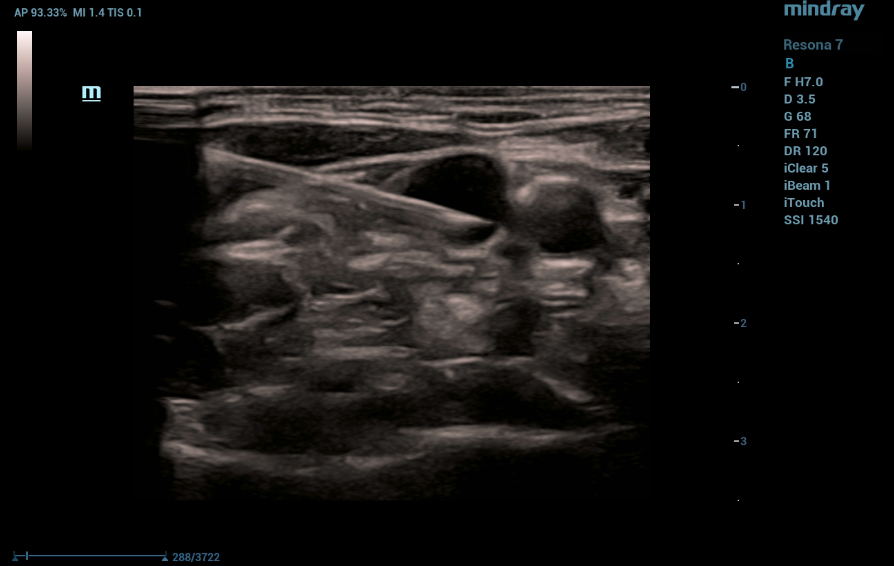

The patient is a woman, 48 years old. She was admitted to an oncology hospital for FOLFOX antitumor treatment, diagnosed with cancer of the stomach antrum pT3N1Mo stage IIB: Before chemotherapy, implantation of a port system with insertion of a catheter through the right subclavian access was indicated. Right jugular vein puncture was performed under ultrasound guidance. The investigations were performed on a Mindray Resona7 expert-class ultrasound machine with a cine recording.

As a result of good visualization of the vein and needle, the puncture was successfully performed, followed by implantation of a saphenous venous port system.